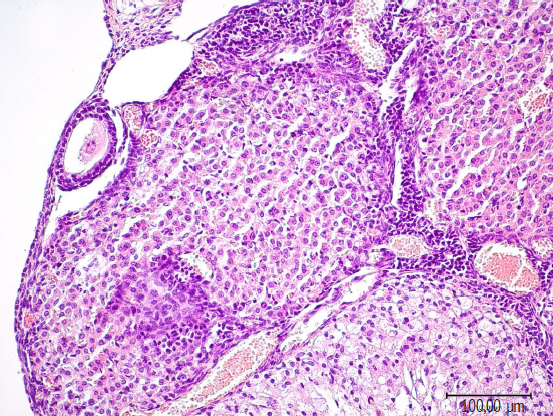

Results. Persistent morphological changes are observed in the ovaries of the offspring of the first experimental group S-50: an increase in the average area of the cortical substance, a decrease in the area of the medulla, an increase in the average number of yellow bodies, an increase in the average number of luteal cells in the yellow body, a decrease in the total number of follicles and atretic bodies, indicating a violation of the folliculogenesis process, an increase in the average diameter of blood vessels demonstrating increased blood circulation. With the introduction of the drug fulvestrant 100 mcg / kg in the second experimental group F-100, morphological changes in the form of an increase in the average area of the cortical substance, a decrease in the average area of the medulla, sclerosis of the stromal component, accompanied by a restructuring of the vascular network with signs of atresia and cystic degeneration of the follicular epithelium in secondary and tertiary follicles are considered on a slice of the ovaries of the offspring.